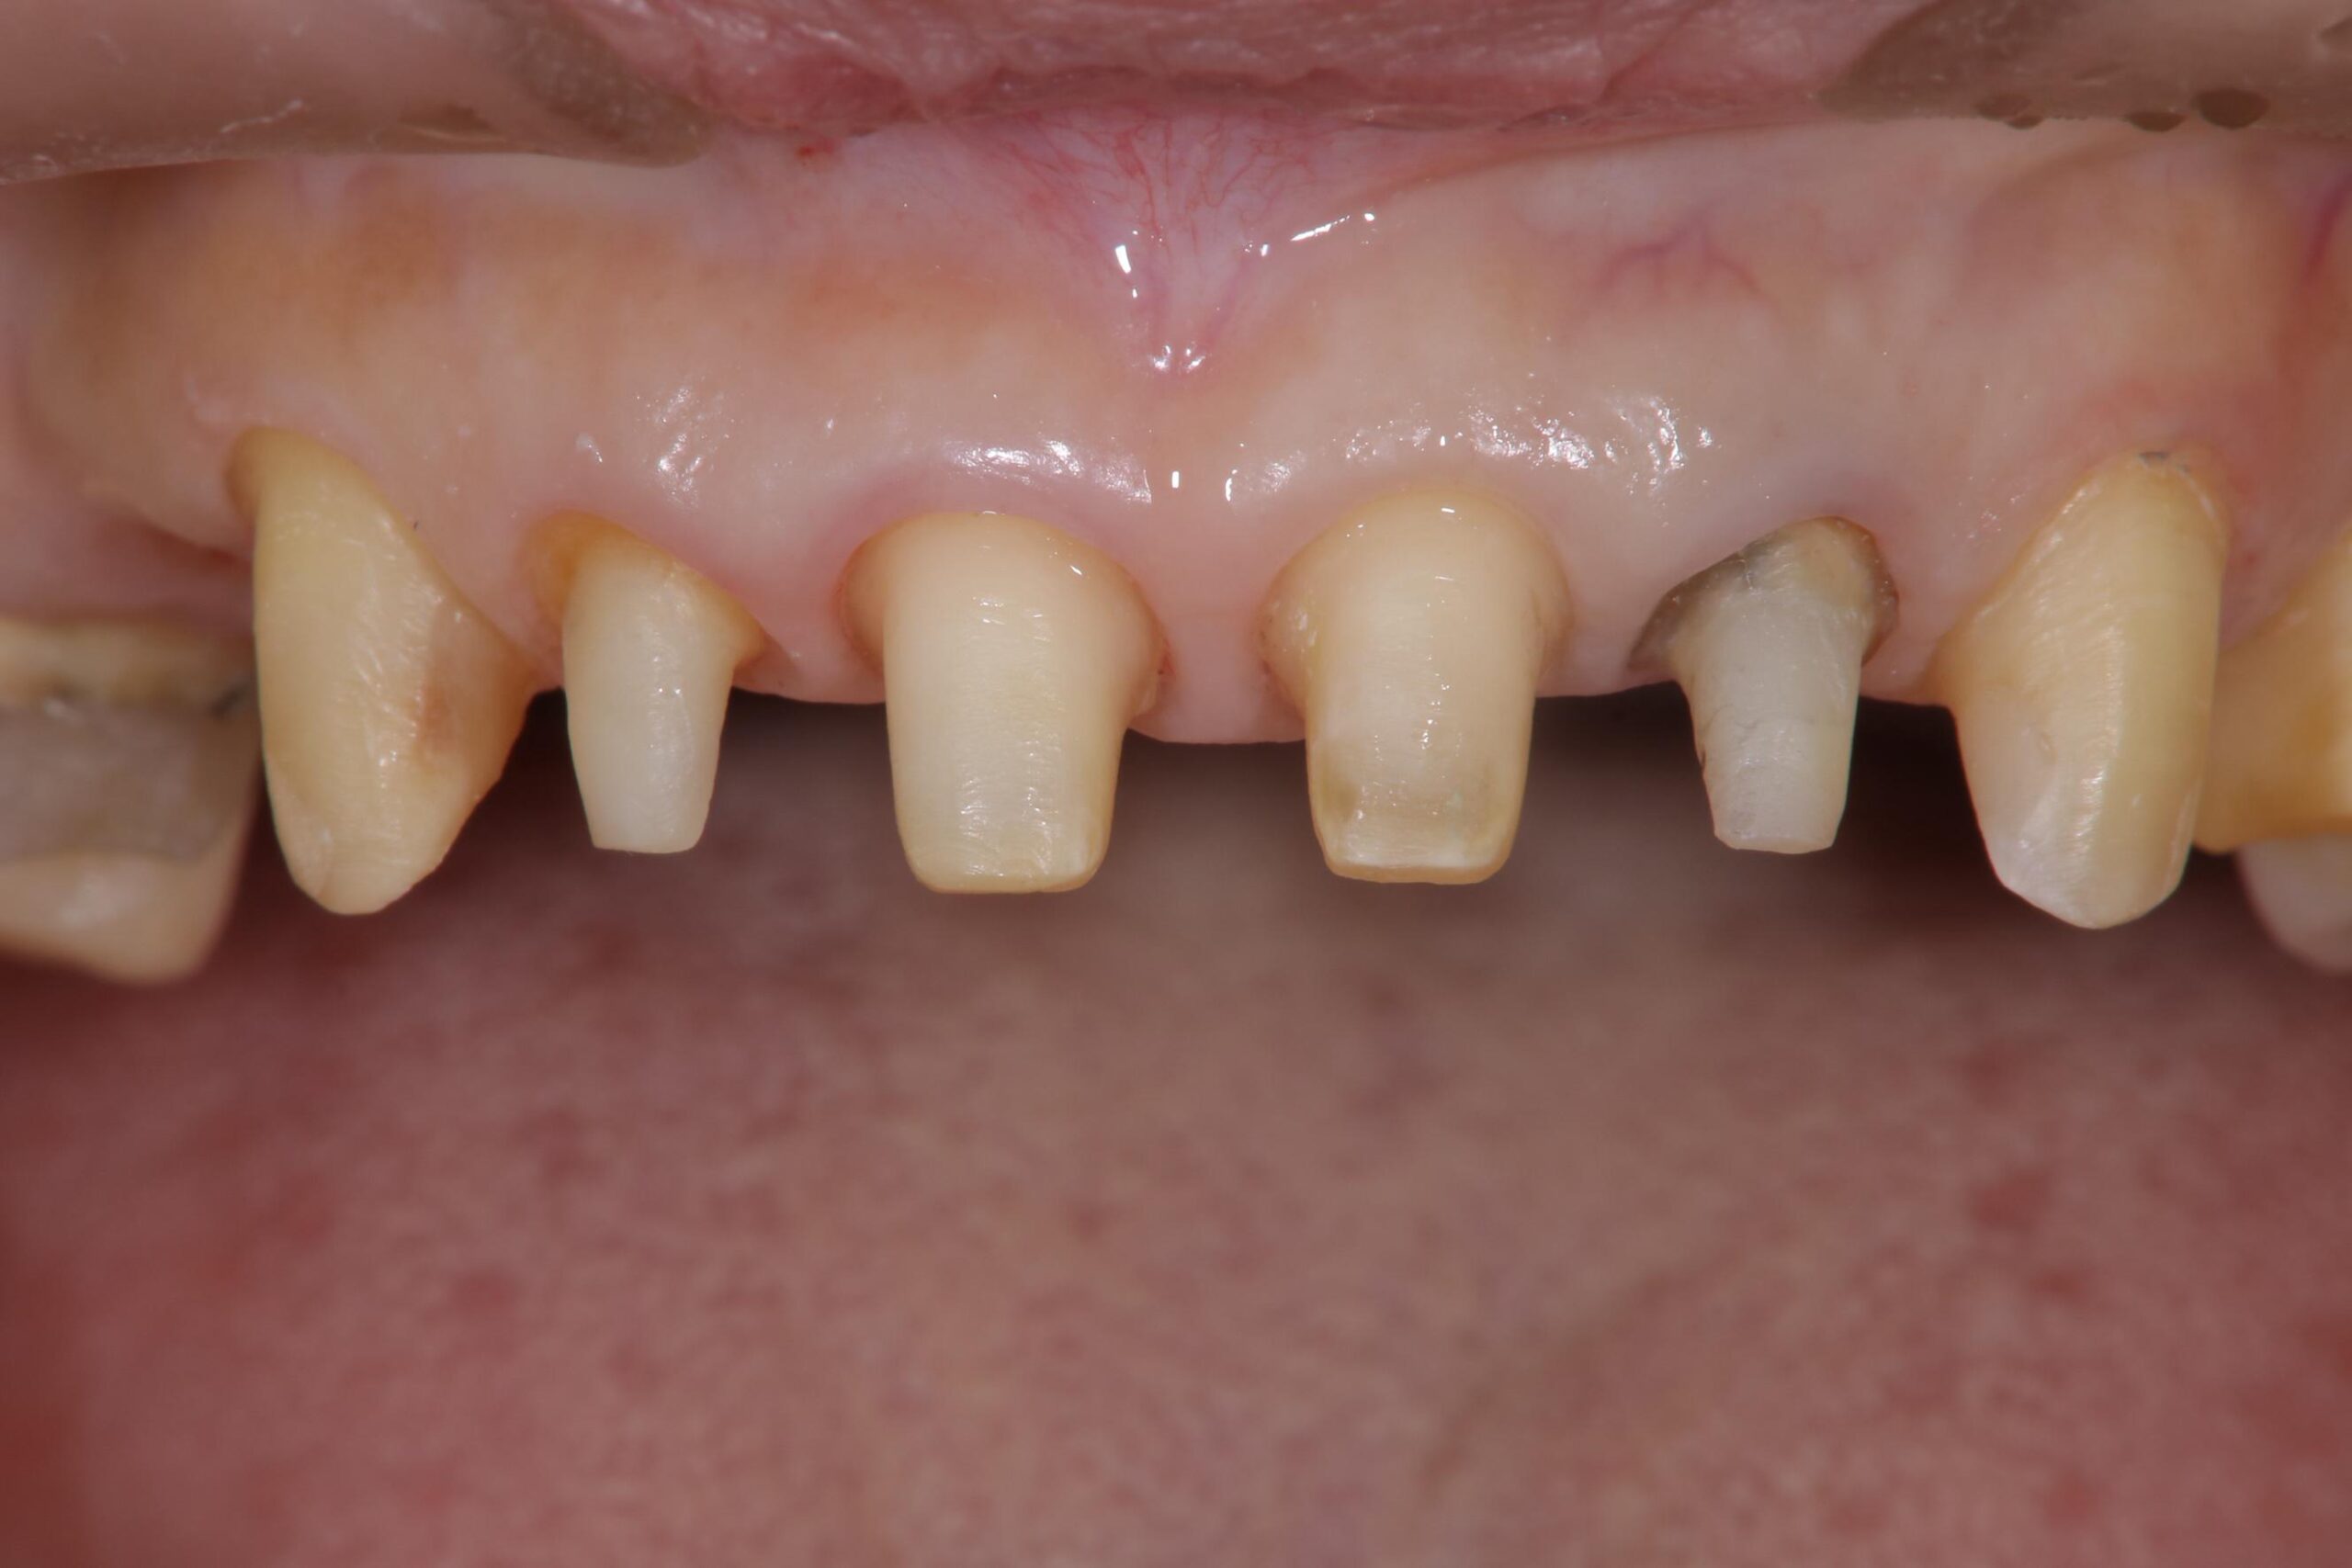

治療前

治療前レントゲン

治療中